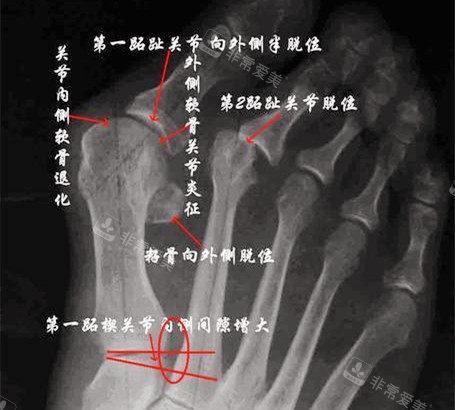

大脚骨X光片